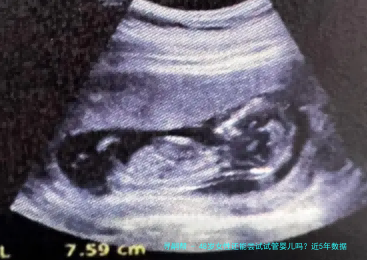

大家好,今天我们来聊聊一个很多女性朋友关心的话题:女人48岁了,还能不能做试管婴儿?说实话,这个问题听起来有点挑战性,但近几年科技发展飞快,让我们用数据说话,一起探讨一下。

首先,年龄对试管婴儿的成功率影响巨大。女性过了35岁,卵巢功能就开始下降,卵子质量也大不如前。到了48岁,自然怀孕的几率几乎为零,但试管婴儿技术提供了另一条路。近5年的数据显示,48岁女性使用自身卵子进行IVF的成功率确实很低,根据美国生殖医学学会(ASRM)2020年的报告,这个年龄段的活产率只有 around 1-2% 。原因很简单:卵子数量减少、染色体异常风险增高,这些都直接影响了胚胎的着床和发育。

不过,别灰心!近5年来,辅助生殖技术有了长足进步。比如,胚胎筛选技术(如PGT)可以帮助检测染色体异常,提高健康胚胎的移植成功率。数据显示,2021年的一项研究指出,48岁女性如果使用捐赠卵子,IVF的成功率可以飙升到50%以上,这简直是个奇迹!我认识一位朋友,她48岁时通过捐赠卵子成功生下了健康宝宝,现在孩子都两岁了,活泼可爱。这告诉我们,年龄不是绝对障碍,关键是要选对方法。